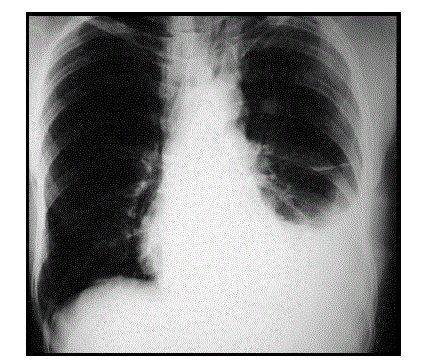

Paciente masculino, 66 anos, com antecedente de infarto agudo do miocárdio em 2013 e miocardiopatia isquêmica em acompanhamento com cardiologista. Procura o pronto-atendimento com queixa de dispneia aos mínimos esforços de instalação progressiva. Relata ainda dor torácica à esquerda que piora com inspiração profunda, além de febre diária há cerca de 01 semana. Realizou radiografia de tórax que diagnosticou presença de derrame pleural: